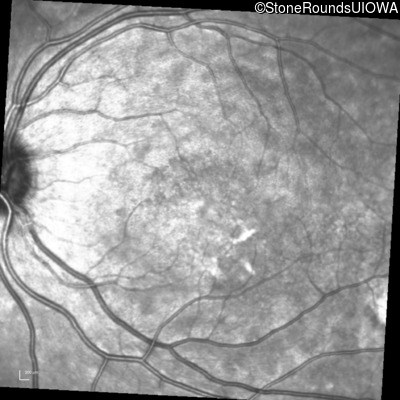

Infrared Fundus Photograph - Left - 20/25 -3 sc

Exemplar